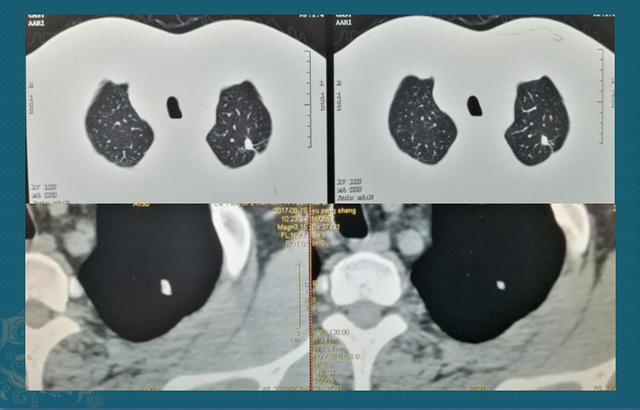

所以专业医生总结:小于2厘米的肺结节,如果见到钙化,基本都是良性

图片

这是一位50岁男子,胸闷体检发现左肺尖小结节灶,形态不规则,边缘有胸膜牵拉,害怕是小肺癌,结果纵隔窗发现密度很高,随访3年无变化,考虑陈旧性肺结核灶。这种的就没必要手术和穿刺了。